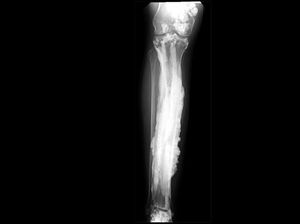

Sebuah kondisi langka bernama melorheostosis membuat pengidapnya memiliki pertumbuhan tulang abnormal. Dari rontgen tulang tampak meleleh seperti lilin.